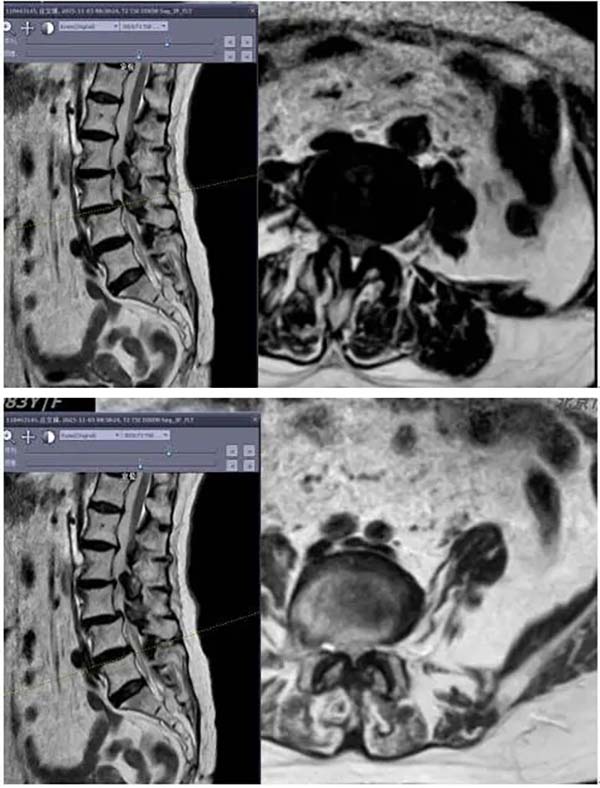

▲术前核磁显示椎管重度狭窄

庄女士因“间断腰痛30余年,近半年加重伴右下肢疼痛麻木行走困难”入院。术前检查示腰椎管狭窄、腰椎滑脱、脊柱侧弯、腰椎间盘突出、腰椎不稳等多种病变,神经受压严重,病情复杂。在接诊后,医院脊柱外科(骨四科)高度重视患者治疗情况,为患者量身定制手术方案。在全面评估患者情况,并与患者及家属充分沟通征得同意后,脊柱外科(骨四科)团队决定采用腰椎后路椎板部分切除减压棘突间内固定装置置入术为患者减轻病痛。